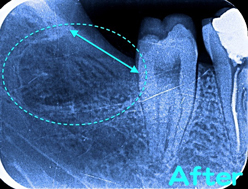

⇔の長さが上の画像に比べて長くなったことからも分かるように、抜歯のために「歯茎」と「骨」を触って出口を広げる必要があります。患者様によって異なりますが、平均1週間〜10日で痛みは軽減します。

根が二股に湾曲して引っ掛っていたため、更に歯を2分割(AとB)することで無事に抜歯が完了しました。

骨の中に埋もれている割合+横向き度合い+根の曲がり具合(左下の写真)→抜歯の難レベル(A→B→C→ウルトラC)から考えると正に“ウルトラC”でした。